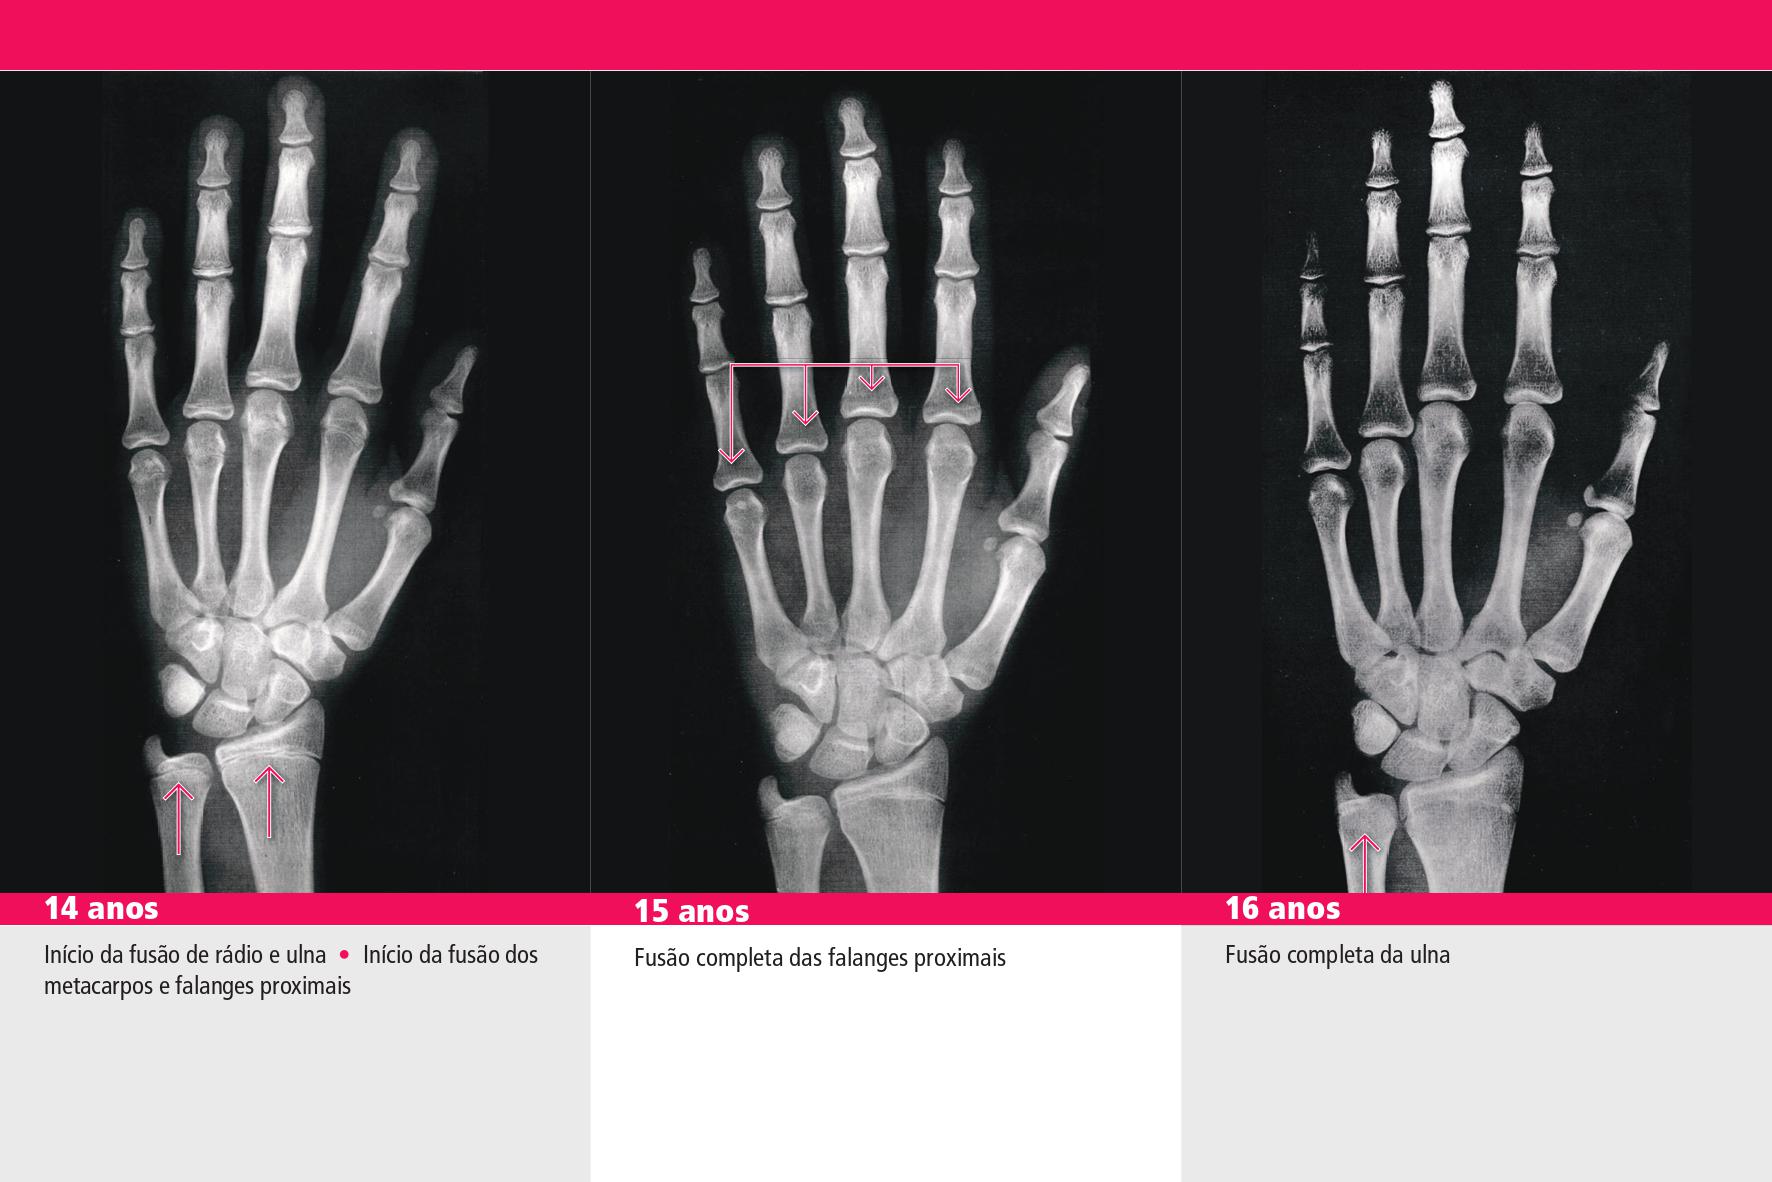

Masculino - 15 anos, 15 anos e 6 meses, 16 anos

Feminino - 14 anos, 15 anos, 16 anos